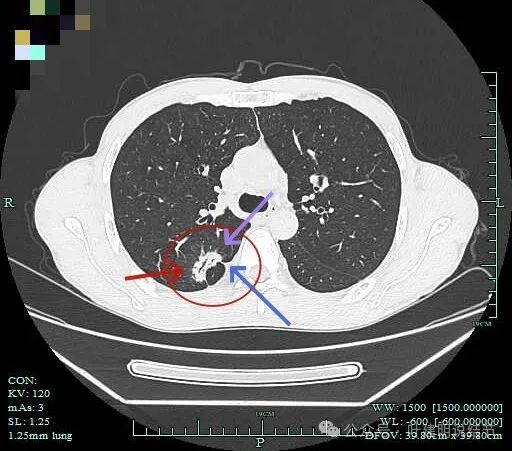

胸膜牵拉,灶内支气管通气征并显僵硬,部分边缘有毛刺征。

有血管进入并异常增粗;病灶有分叶征,有毛刺征,也有胸膜牵拉征。

病灶有细毛刺征,感觉有收缩力。

实性成分为主,边上少许磨玻璃成分。

叶间胸膜牵拉。

这个病灶是非常典型的恶性的,总体上基本上是实性成分,但边上仍有少许磨玻璃,而磨玻璃成分有分叶与细毛刺,病灶内部有支气管通气征,且支气管显僵硬,又有异常增粗的血管进入。再加上胸膜牵拉、叶间裂牵拉,整体轮廓较清,周围肺野清爽,没有卫星灶。所以基本上就是浸润性癌了的。